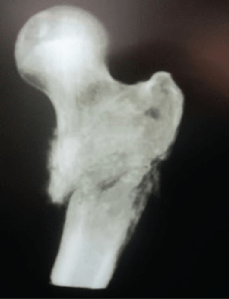

Cirurgia Quadril e Joelho

Dr. Paulo Alencar

Enfoque:Cirurgia da Doença Degenerativa e Banco de Tecidos

Reconhecido pela SBCJ e SBQ

(Sociedade Brasileira de Cirurgia do Joelho e Quadril)

Ortopedia Oncológica

Dr. Márcio Moura